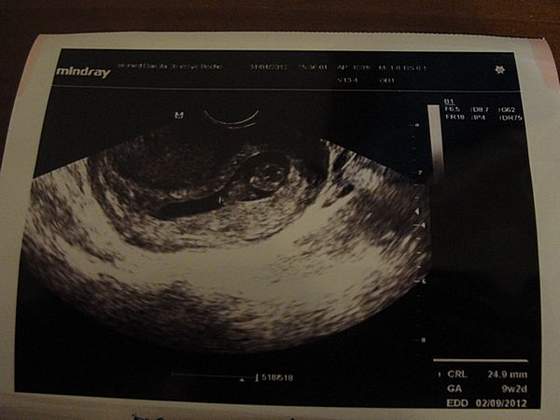

usg2.jpg

O, udało się :-D:-D Widać? Zdjęcie z crl nieco mniejszym, ale w ten sposób widać rączki i nóżki.:-D